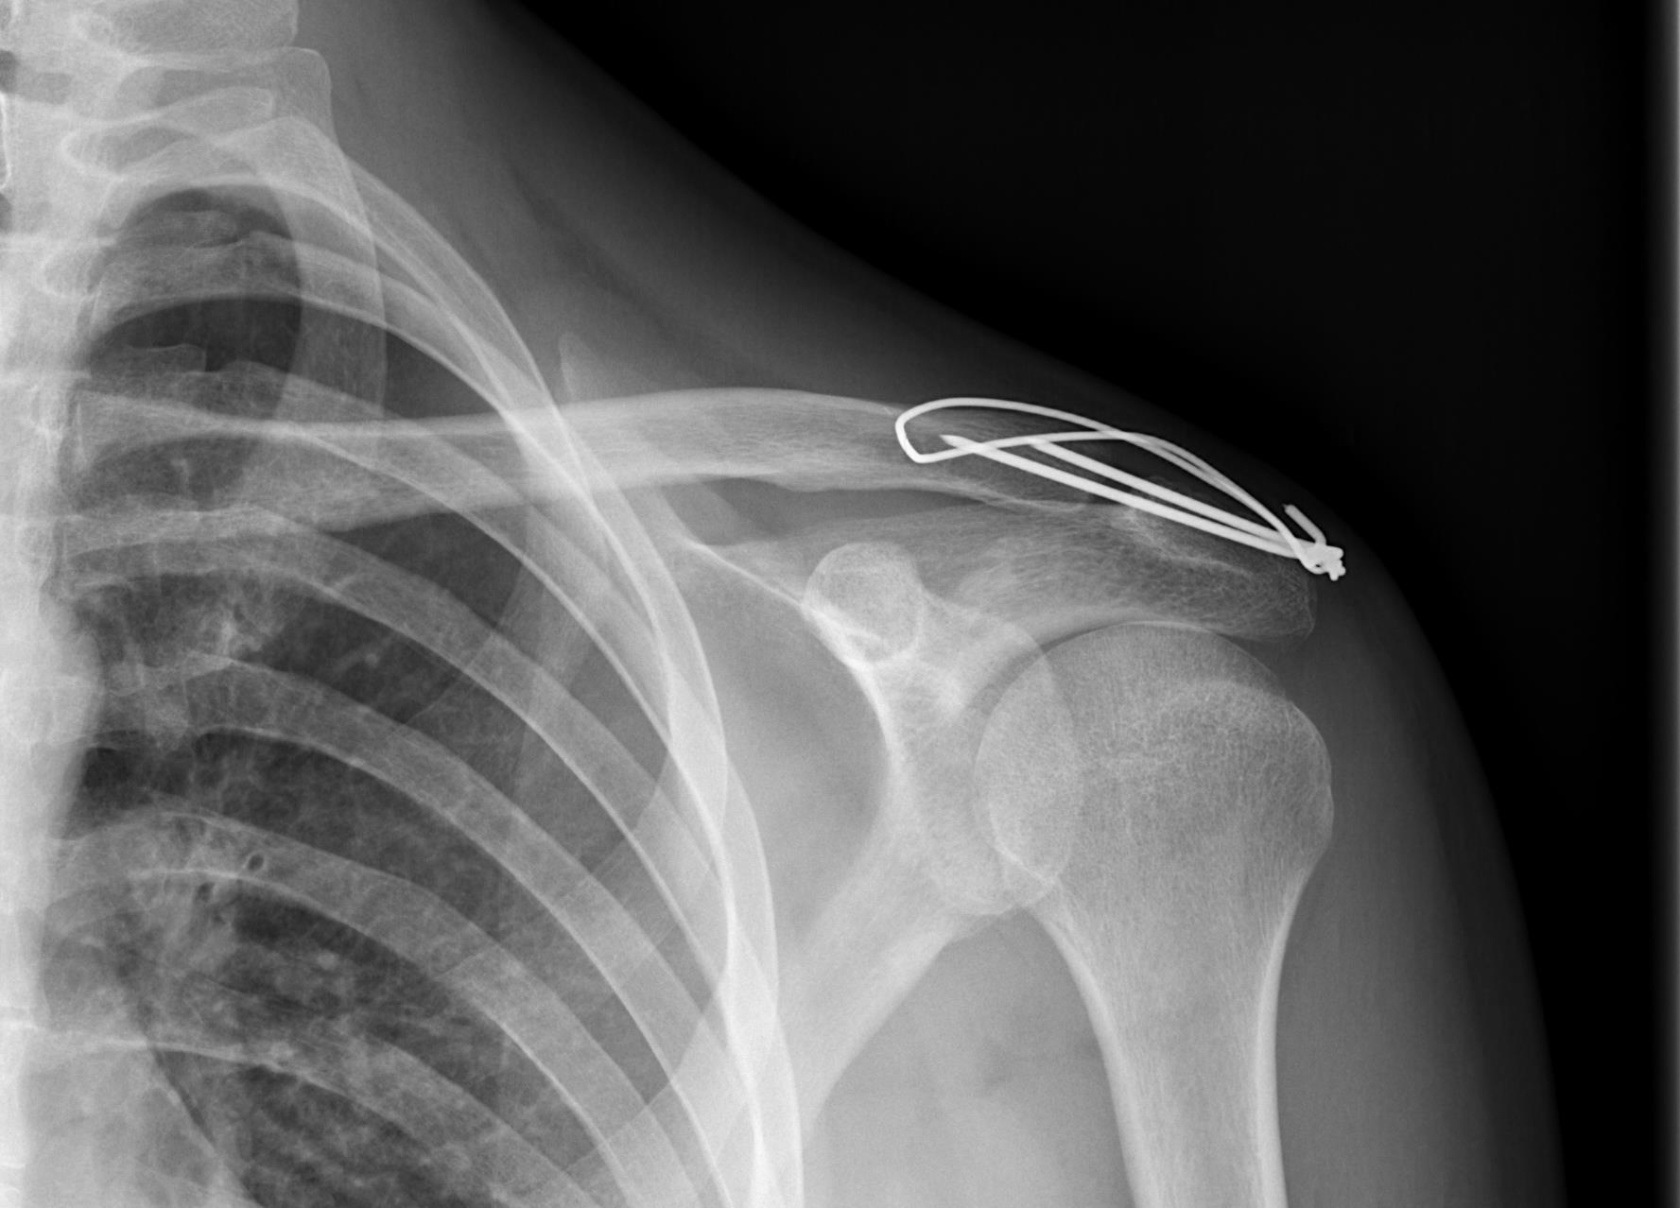

Tomasz 39 lat wynik RM stawu barkowego Wzmozenie ilosci plynu stawowego. Glowa kosci ramiennej przemieszczona nieco ku tylowi,nie centruje w panewke. Poszerzenie szpary stawu barkowo obojczykowego; obrzek szpiku kostnego konca barkowego obojczyka I wyrostka barkowego lopatki.Podwyzszenie sygnalu I poszerzenie obrysu... Tomasz 39 lat wynik RM stawu barkowego Wzmozenie ilosci plynu stawowego. Glowa kosci ramiennej przemieszczona nieco ku tylowi,nie centruje w panewke. Poszerzenie szpary stawu barkowo obojczykowego; obrzek szpiku kostnego konca barkowego obojczyka I wyrostka barkowego lopatki.Podwyzszenie sygnalu I poszerzenie obrysu sciegna miesnia nadgrzebieniowiego w okolicy przyczepu do guzka wiekszego kosci ramiennej . Sciegno miesnia podgrzebieniowego w zatartych zarysach. Obrzek miesni nad-i podgrzebieniowego oraz niewielka ilosc plynu w ich otoczeniu.Sciegno glowy dlugiej miesnia dwuglowego ramienia o prawidlowym sygnale I przebiegu; niewielkie wzmozenie ilosci plynu w jego pochewce.Obrabek stawowy wydaje sie byc prawidlowy. Moje pytanie czy konieczna jest Artroskopia?